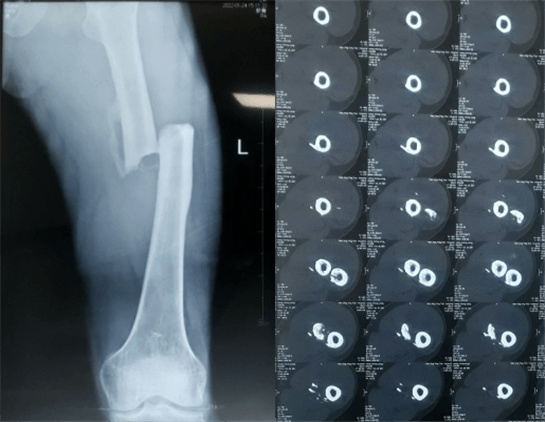

患者:男性,43歲,左股骨干骨折髓內釘內固定術

股骨是下肢的主要負重骨,有其特殊的解剖關系,周圍肌肉發達,因此一旦股骨干骨折后如果治療不當,容易造成肌肉牽拉,導致畸形和功能障礙。治療股骨干骨折,必須遵循恢復肢體的長度及力線,無旋轉,盡量行以微創,保護骨折局部血運,促進愈合。髓內釘對骨折的固定能夠達到較大的穩定性和堅固性,可以減少醫源性污染,減少軟組織分離及周圍血供破壞,有利于骨折早期愈合,是治療股骨干骨折的首要治療方法。

術前檢查